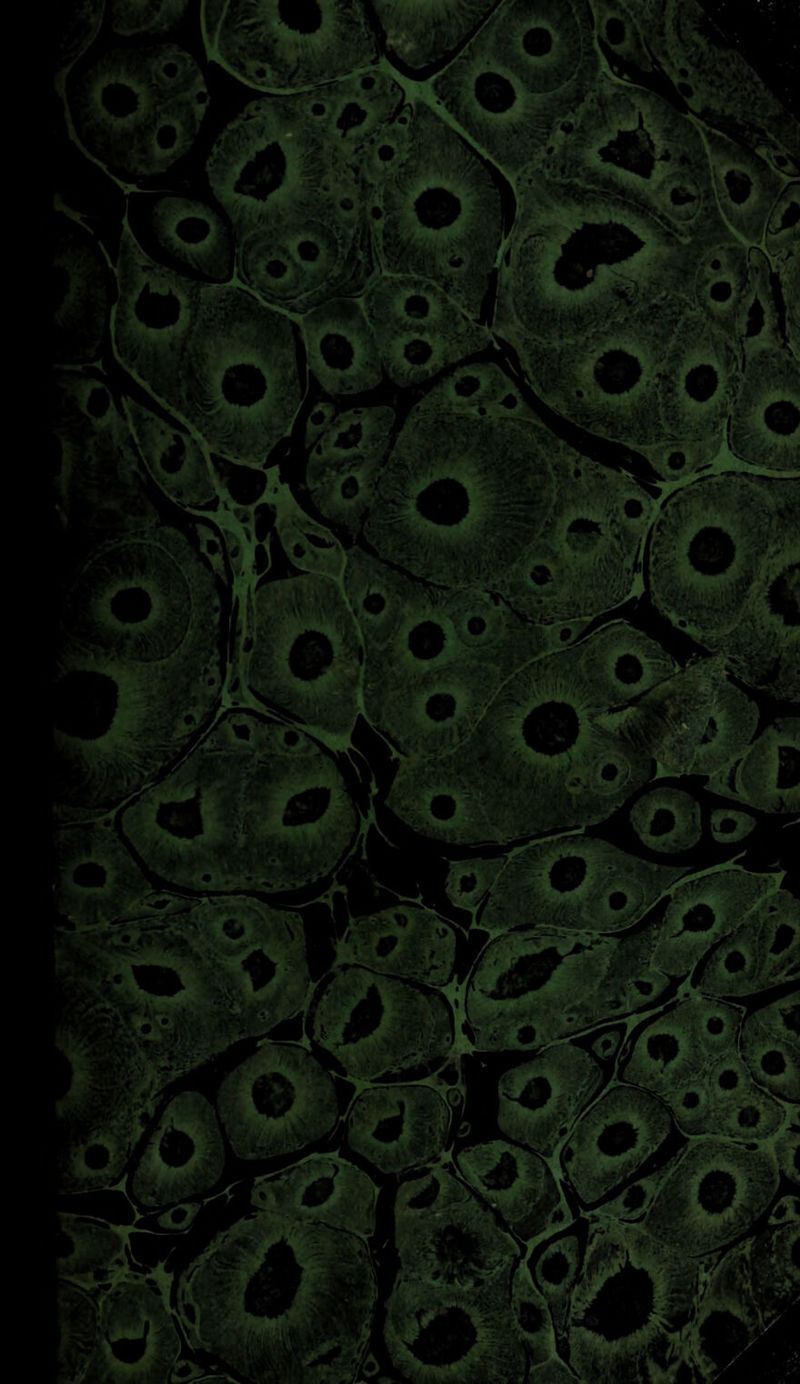

Dictionnaire de médecine-pratique et de chirurgie / [M.J.F. Alexandre Pougens].

- Pougens, M. J. F. Alexandre.

- 1820